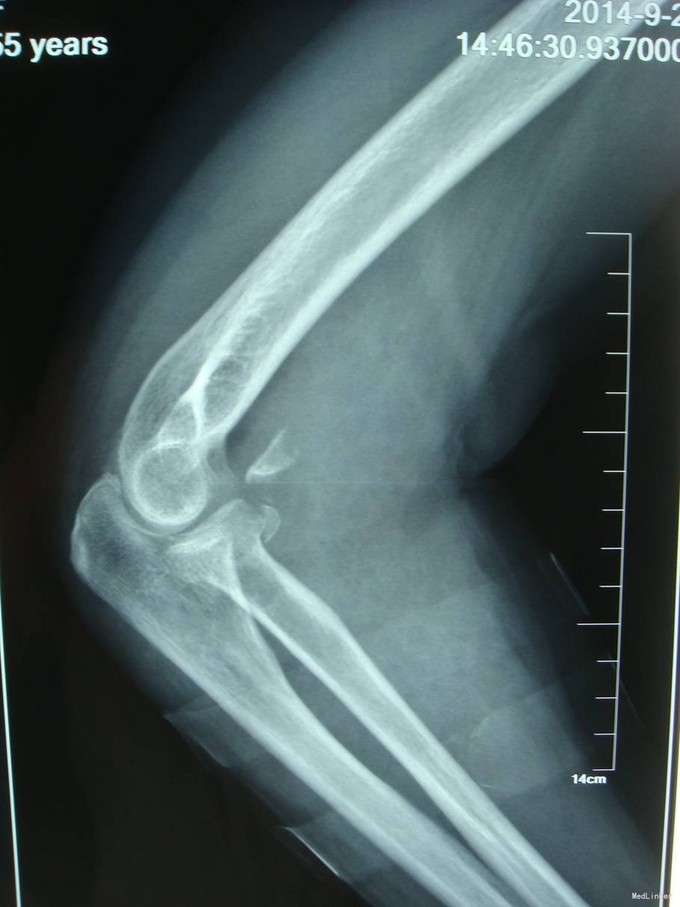

主诉:摔伤后右肘部疼痛10小时 患者自述2014-9-2 早8点自己走路时不小心摔倒,右肘部着地,导致右肘部疼痛、肿胀、活动受限,于当地医院拍片诊断为“右肘关节脱位”,给予手法复位, 为求进一步治疗来我院,诊断为“左肘关节骨折”,并收入我科,患者自受伤以来,无发热,无呼吸困难,无腹痛腹泻,饮食睡眠正常,大小便未见异常。

患者步入病房,左肘关节肿胀明显,压痛(+),骨擦音及骨擦感(+),左上肢感觉未见异常,左手指活动正常,左桡动脉搏动可触及。

患者入院后左肘关节石膏固定,左肘关节对症消肿等治疗。1周后完善检查后查无明显手术禁忌症后行左桡骨小头骨折切开复位内固定术。